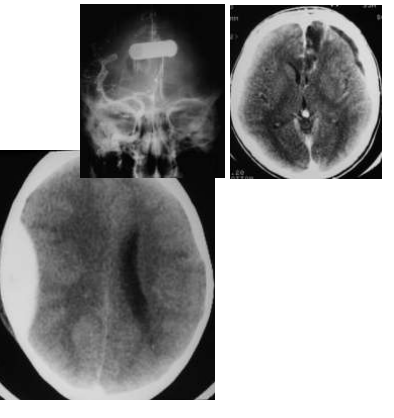

Na contusão cerebral (Figura 4 - esquerda) o achado é o de uma hipodensidade no local associada a pequenos focos de hiperdensidade (sangue), de diferentes tamanhos. Na evolução do paciente, pode ocorrer aumento da hipodensidade (edema) e do tamanho da área de hemorragia. A lesão axonal difusa (Figura 4 - direita)‚ caracterizada por pequenos focos de hemorragia no centro semi-oval, no corpo caloso, no tronco cerebral e nos pedúnculos cerebelares e, eventualmente, pode ocorrer também hemorragia intraventricular de pequena ou moderada intensidade. Quando a lesão é isolada não se observa diminuição das cisternas basais e dos ventrículos; nestes casos, é chamativa a gravidade do paciente associada a poucas alterações visíveis na tomografia.

Os hematomas agudos (Figuras 5 e 6) são visibilizados, como uma lâmina hiperdensa. Esta lâmina é convexa em relação ao parênquima no hematoma extradural, pois a aderência da dura-máter ao osso, limita o seu crescimento. Nestes, geralmente observa-se traços de fratura quando são realizados cortes com janela especial para visualização de osso. No hematoma subdural agudo, esta lâmina é côncava, pois não há limitação para o seu crescimento e o coágulo acompanha a curvatura do córtex cerebral. No hematoma subdural crônico (Figura. 6 - direita), a lâmina é hipodensa ou hiperdensa e, eventualmente, isodensa. Com a injeção do contraste endovenoso existe uma demonstração de sua cápsula ao redor.